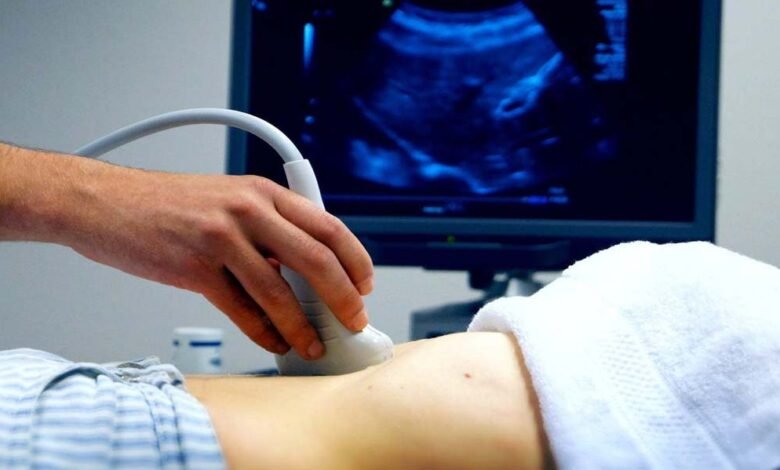

विशेषज्ञों के अनुसार, गर्भपात एक वैज्ञानिक प्रक्रिया है, जिसे तय समय-सीमा और डॉक्टर की निगरानी में ही किया जाना चाहिए। सोनोग्राफी और जरूरी जांच के बाद ही दवा दी जानी चाहिए। डॉक्टरों का कहना है कि अधूरे गर्भपात के कारण अत्यधिक खून बहने से महिलाओं का ब्लड प्रेशर गिर जाता है और शरीर का सिस्टम फेल होने लगता है। कई मामलों में जान तक चली जाती है।